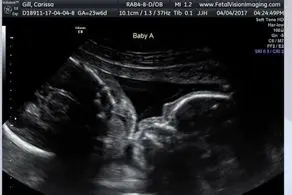

به گزارش منیبان؛ یکی از کاربران فیس بوک با انتشار تصاویر ناراحت کننده از نوزاد سقط شده است ثابت کرد که این باورها کاملا غلط است و به هیچ وجه نمی توان سقط جنین را در ماههای اول بارداری بدون ایراد دانست.“فلیشیا ” و همسرش 13 سال موفق به بچه دارشدن نشدند و تصمیم به انتخاب کودکان بی سرپرست گرفتند ، آنها 3 دختر را به فرزند خواندگی انتخاب کرده و زندگی جدیدی با انها آغاز کردند .مدت کوتاهی از این ماجرا نگذشته بود که خبر باورنکردنی آنها را خوشحال کرد ، فلیشیا باردار بود .فیلیشیا می گوید:در کمال ناباوری صبح روز بعدی که ما در دادگاه برگه پذیرفتن فرزند خواندگی 3 دختربچه را امضا کردیم متوجه این ماجرا شدیم که خداوند فرزندی به ما خواهد داد و من باردار هستم.8 ماه بعد پسربزرگم متولد شد و مدتی بعد متوجه شدم که دوباره باردار هستم ولی این بار بارداری پردرسری داشتم.چند هفته بعد از خبر بارداری به دلیل خونریزی شدید به بیمارستان رفتم ولی تشخیص اشتباه پزشک مرا متقاعد کرد تا به خانه بازگردم و روز بعد نوزادم را که تنها 14 هفته و 6 روز داشت سقط کنم.عکسهای او را منتشر کردم تا همه بدانند نوزادی در این دوره از مدت زمان باداری چطور شبیه یک انسان کامل شکل گرفته است و به این راحتی نمی توان با کروتاش آن را سقط کرد.